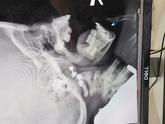

Дочь начала храпеть, пошли к Лору, она отправила на снимок. В итоге 3 степень (((но у нас подозрение на аллергический АД, а она сказала аллергики лучше поддаються лечению, поэтому на месяц выписала назонекс, если не станет лучше, то только удаление … Читать далее